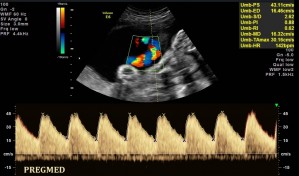

Analiza przepływu przez tętnicę pępowinową określa ryzyko hipoksji czy kwasicy u płodu. Badanie to jest wykonywane, gdy istnieje podejrzenie zaburzeń wewnątrzmacicznego wzrostu płodu. Dokładne oszacowanie jego stanu wymaga oceny także innych naczyń, najczęściej tętnicy środkowej mózgu płodu (MCA) oraz przewodu żylnego (DV). Cechy patologiczne podczas badania przepływów przez tętnicę pępowinową to brak przepływu rozkurczowego lub odwrócony przepływ rozkurczowy.

Fot.1. Prawidłowe spektrum przepływu w tętnicy Fot.2. Prawidłowe spektrum przepływu w tętnicy pępowinowej w 23 tyg. ciąży. pępowinowej w 29 tyg. ciąży.

Fot.3. Prawidłowe spektrum przepływu w tętnicy Fot.4. Prawidłowe spektrum przepływu w tętnicy pępowinowej w 25 tyg. ciąży. pępowinowej u jednego z bliźniąt w 29 tyg. ciąży.